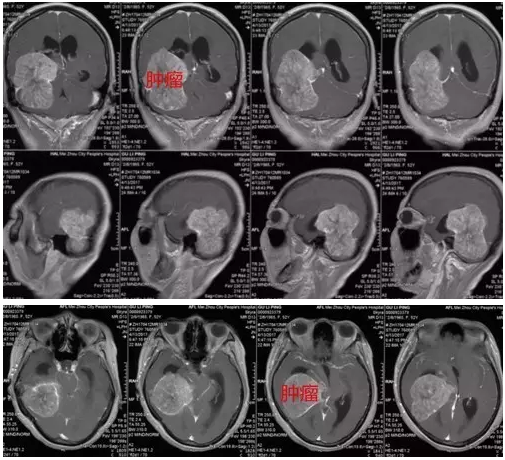

图3:MR显示肿瘤强化明显,大小约66mm×58mm×73mm

血管周细胞瘤临床表现无特异性,肿瘤多生长至一定大小才产生临床症状,头痛为最常见的症状,可能与肿瘤扩张、压迫血管影响血供或直接压迫神经有关,此时肿瘤已较大甚至出现脑积水和小脑扁桃体下疝,增加了手术难度。本例患者头痛1年,未有特征症状,入院前5天才出现恶心呕吐及肢体乏力症状,检查发现时病变已达66mm×58mm×73mm。

中枢神经系统血管周细胞瘤MR表现与脑膜瘤相似,肿瘤较大时外形多呈分叶状,可见囊变坏死,出血及流空血管,增强后肿瘤实质部分明显强化,坏死囊性变区无明显强化。“脑膜尾征”较少见。